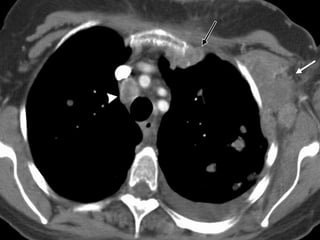

5. Subaortic LNs (aortopulmonary window LNs)

6. para-aortic LNs • Anterior & lateral to the ascending thoracic aorta & aortic arch.